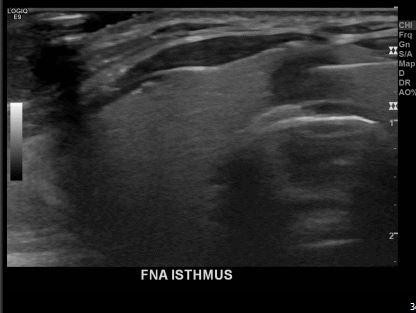

상기환자  외부검사이상소견으로 내원하신 40대 초반 여성분으로 의심스러운 갑상선혹 세포검사진행후 갑상선암으로 진단되었습니다